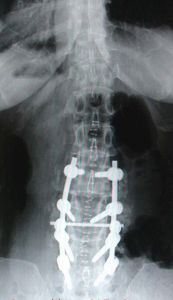

正位X線片常顯示腰椎輕度側彎,關節突間關節間距離變小,有退行性改變。側位X線片顯示椎管中央矢狀徑常小,小於15mm就說明有狹窄的可能。必要時可進行腰椎穿刺,奎肯試驗,腦脊液化驗,及脊髓造影。脊髓造影是診斷本症的可靠方法。正位片可清楚顯示硬脊膜腔的大小,如出現有條紋狀或鬚根狀陰影,表示馬尾神經根有受壓現象,或全梗阻,如影柱呈節段性狹窄或中斷,表示為多發性或全梗阻。

CT、MRI檢查:鞘膜囊和骨性椎二者大小比例改變,鞘膜囊和神經根受壓,硬膜外脂肪消失或減少,關節突肥大使側隱窩和椎管變窄,三葉狀椎管,弓間韌帶、後縱韌帶肥厚。

手術以全椎板截除,徹底減壓為主。所謂徹底減壓是指在截除椎板時不但要夠高夠寬,而且要解除椎體後部(椎管前部)和側隱窩的增生骨質,以便徹底解除馬尾及神經根的一切壓破。

③多數混合性椎管狹窄症。手術要求解除對硬脊膜及神經根的壓迫。操作包括椎板切除、肥厚黃韌帶切除、上關節突部份切除、神經根管擴大及神經粘連松解等。徹底減壓的標準是恢復硬脊膜搏動、神經根滑動範圍在1cm以上。對術前有椎間關節不穩定、雙側椎板及關節突要融合。